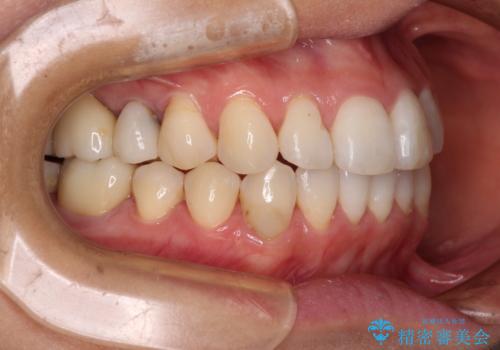

- 捻れた前歯と目立つ銀歯を気にして来院された患者様です。

歯列不正は軽微であったため、インビザライン・ライトにて改善することとしました。

左下大臼歯は根管治療が必要であったため、矯正治療前に根管治療を行い、その後矯正治療を行うこととしました。

矯正治療後には期にある銀歯を全てセラミッククラウンなどで補綴治療することとしました。

インビザライン・ライトによる矯正治療であったので、時間をかけずに治療を終えることができました。

口を開ける度に目立っていた銀歯もセラミックで自然な口元の印象となりました。